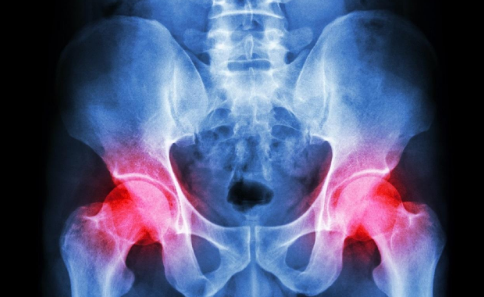

引起骨癌的常见因素有哪些?

近年来,骨癌已经成为危害社会和人类健康的一大疾病之一,它给人类带来了极大的痛苦和困扰。骨癌的出现与生活中很多因素有一定的关系,那么,引起...

骨癌应该如何进行治疗?

说到骨癌,相信大家应该都不会感到陌生了,骨癌的发病率越来越高,严重威胁着每个人的身心健康,并且对于骨癌患者朋友们来说,治疗骨癌也需要用很...